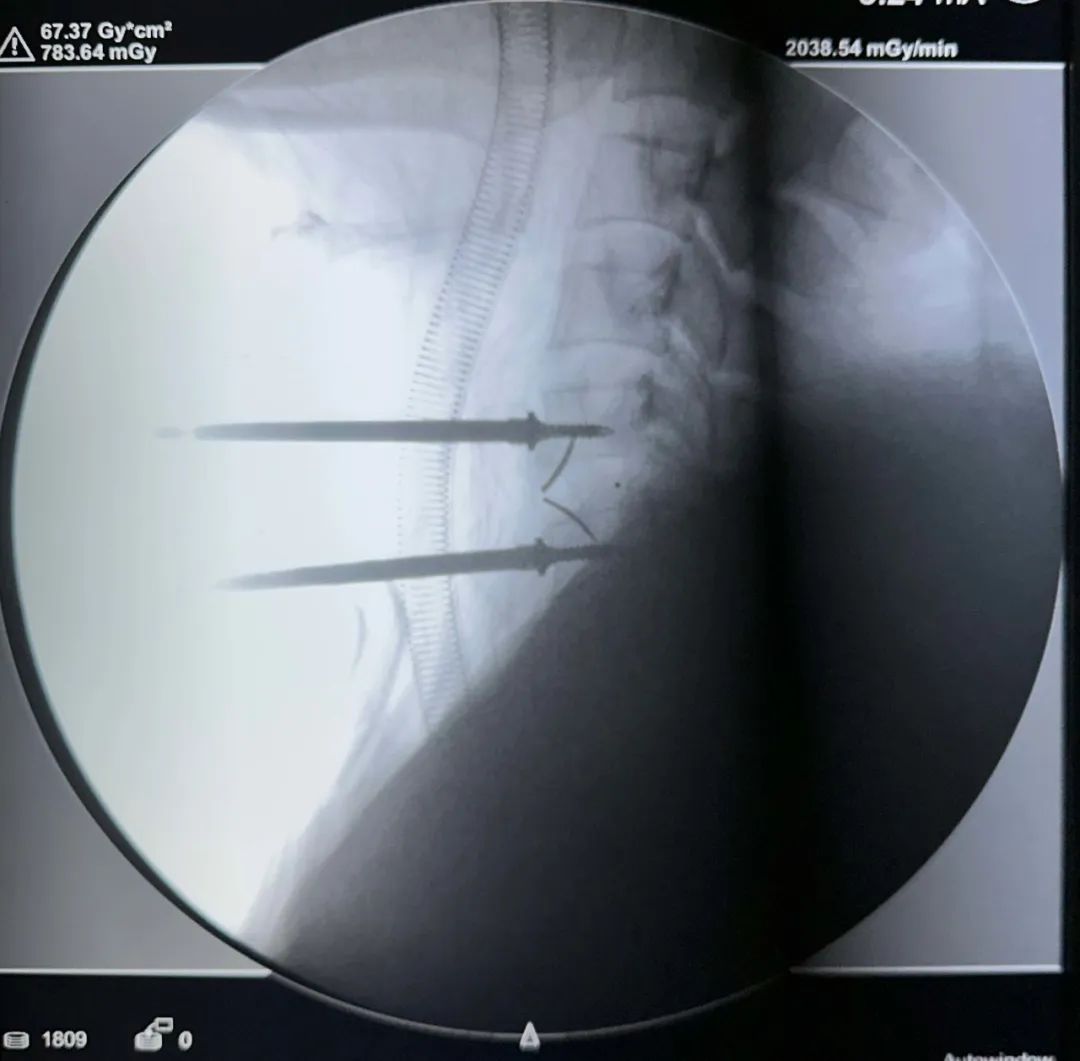

術(shù)中影像

節(jié)段確認(rèn)——

融合器打入及確認(rèn)——

固定夾打入及確認(rèn)——